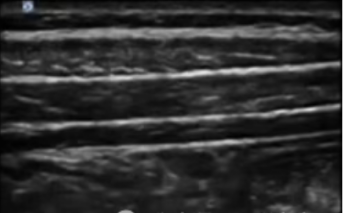

超声引导下TAP阻滞借助超声可视化技术,能清晰地辨别腹部皮肤、皮下脂肪、各层肌肉结构以及周围脏器位置,动态监测穿刺针走向和药物扩散情况,穿刺成功率高,并发症发生率低,安全性更有保障。